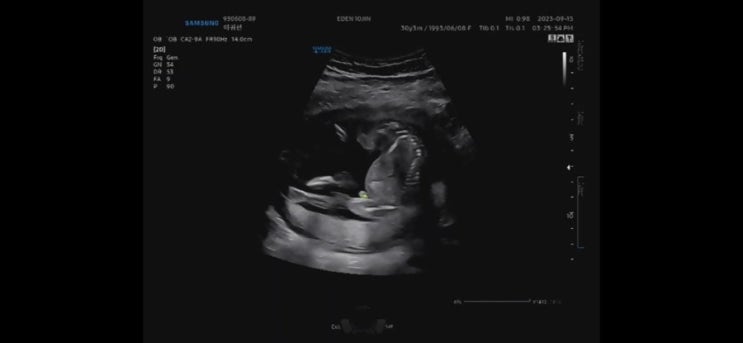

[15W~16W] 에덴병원 통합 기형아검사, 안정기 돌입! 자몽이의 성별은? 장꾸맘 각도법 결과

15주! 머리카락이 자라기 시작하는 15주 엄마 머리숱 닮으면 많을꼬야~~ 근데 아빠도 어릴적 사진 보니까 ...